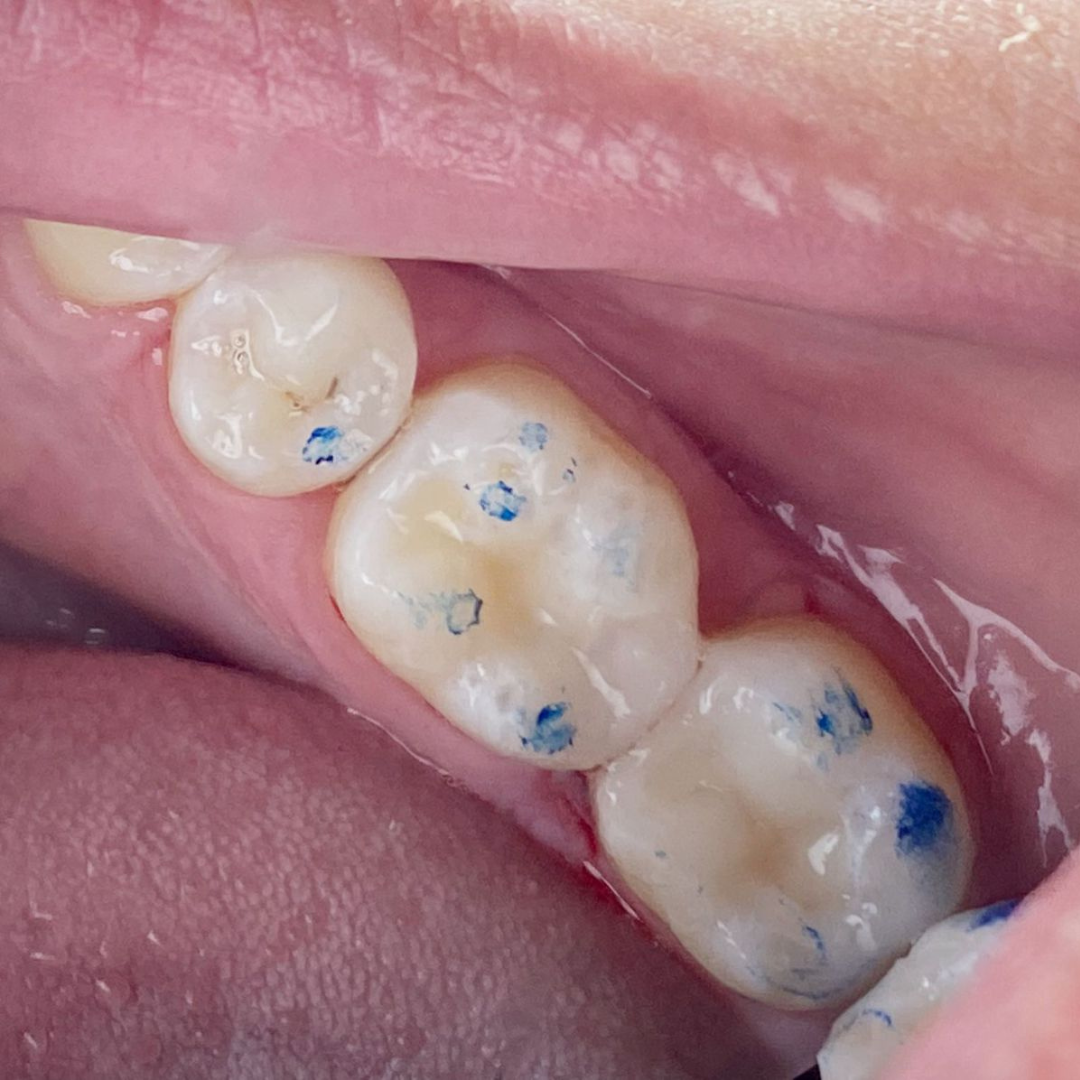

Throughout my studies, I immersed myself in learning, not just from books, but through hands-on experience at a local dental clinic. I spent countless hours there, treating patients and gaining invaluable practical skills. The joy and relief I saw in their eyes after each session were my greatest rewards. My humility and dedication earned me the love and respect of everyone around me.